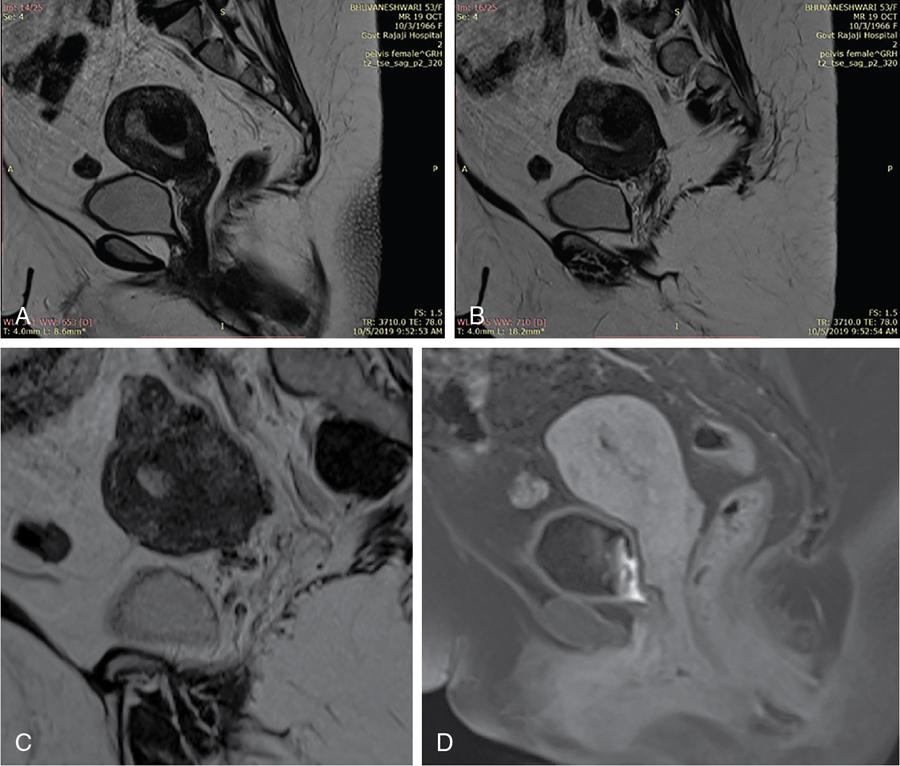

John De Lindsay, Sumathy, Vasumathy, Usha nandhini Ganeshan, N. Sundari ENDOMETRITIS Endometritis is defined as the inflammation of the uterine endometrial layer. Endometritis is frequently observed in the pregnant and postpartum population. Pelvic inflammatory disease (PID) and invasive gynaecological procedures are the most common causes of acute endometritis in nonobstetric population. Endometritis is the most complex asymptomatic and often presents with subclinical form of PID. Ultrasound may reveal minimal particulate endometrial fluid with mildly thickened endometrium showing increased vascularity. Computed tomography (CT) findings include a diffusely bulky uterus due by inflammation, mild fluid distension of endometrial cavity and striking endometrial enhancement in comparison to the adjacent myometrium due to mucosal hyperaemia. ‘Indistinct uterine border’ sign is observed in patients with endometritis, which is defined as the loss of distinction between the uterus and the adnexa. Since it is also observed in the cases of endometriosis or malignancy, it is a nonspecific sign. The age of the patient, clinical presentation, and the biopsy of endometrium helps in differentiating endometritis from other pathologies. UTERINE ARTERIOVENOUS MALFORMATION Uterine arteriovenous malformation (UAVM) is an abnormal connection between the arteries and the veins of the uterine myometrium without an intervening capillary bed. They were first reported by Dubreil and Loubat in 1926. They can be congenital or acquired. Even though UAVMs have varied presentation, uterine bleeding is the most common one. They often follow a pregnancy event. Episodic or occasionally torrential vaginal bleeding can occur. Congestive heart failure secondary to vascular steal can be a rare presentation due to a large UAVM. UAVM is most commonly an acquired condition. Pregnancy has a significant role in their pathogenesis. It is most commonly observed in reproductive age group. UAVMs are frequently observed in the postpartum period, few months after spontaneous miscarriage, surgical evacuation of uterus for miscarriage or medical termination of pregnancy. Infection, inflammation, retained products of conception (RPOC), gestational trophoblastic disease (GTD), gynaecologic malignancies, pelvic trauma and exposure to diethylstilboestrol can also lead to UAVMs. Few cases are also reported in young adolescent and postmenopausal females. UAVMs rarely are congenital and may be also associated with AVMs in other locations. Congenital AVMs Congenital AVMs have a central nidus with multiple feeding arteries and draining veins. In this condition, there is extension of the lesion beyond that uterus and multiple pelvic vessels other than uterine vessels draining into them. That cause of congenital AVMs are thought to be due to failure of embryological differentiation. With the progression of pregnancy, these vessels have the propensity to invade surrounding structures. Iatrogenic Acquired AVMs When the venous sinuses are incorporated into the scars of myometrium after the necrosis of chorionic villi, acquired malformations may arise. In contradiction to congenital AVMs, acquired AVMs multiple fistulous communication between the intramural arteries and the venous plexus. These AVMs may have either dual blood supply or a single supply from the uterine arteries and presents without nidus. Vaginal bleeding caused by pregnancy-related causes must be differentiated from UAVMs. Surgery/evacuation is the appropriate management for the former and the same is contraindicated in the UAVMs and hence an accurate definitive diagnosis is important. Grey-scale ultrasound findings are nonspecific and they are subtle heterogeneity of myometrium with multiple tubular or ‘spongy’ anechoic or hypoechoic areas. In spite of varied presentations such as an intramural uterine, endometrial or cervical mass-like lesions or prominent parametrial vessels, it has minimal mass effect. On colour Doppler, within the myometrium, a region of increased vascularity and most commonly with aliasing is seen. A group of vessels traversing the myometrium running perpendicular to and into the endometrium, from the arcuate vessels, can be seen. It is not specific, as they are also observed in RPOC, GTD, placental polyp and vascular endometrial neoplasm. In pulsed Doppler, multidirectional turbulent flow with intense vascularity can be seen with high peak velocity (mean peak systolic velocity [PSV] = 136 cm/s) and low resistance (mean resistance index = 0.3) flow. The arteries have low pulsatility while the draining veins are pulsatile and show high velocity flow. Magnetic resonance imaging (MRI) offers noninvasive confirmation of the diagnosis of UAVM. T1-weighted and T2-weighted images show multiple serpentine signal voids along the uterine wall, endometrial cavity and parametrium. Contrast-enhanced MR angiography shows intensely enhancing complex serpentine abnormal vessels with early venous return. Catheter angiography can be reserved only for women who require embolization of the AVM. The consent for both diagnostic angiography and therapeutic embolization should be obtained simultaneously to avoid repeat therapeutic procedures. Management of UAVM depends on: UAVM can be treated with medical therapy with hormones, uterine artery embolization or with definitive hysterectomy. Once the diagnosis of a UAVM is confirmed, the treatment option depends on the clinical condition of the patient. The size of the AVM bears no correlation to the need for embolization. Timmerman et al. found that AVMs having PSV of at or above 0.83 m/s, most often requires embolization. Also, the vascular malformation with PSV value below 0.39 m/s does not require embolization. Placental bed subinvolution, enhanced myometrial vascularity (EMV), molar pregnancy or RPOC are the other causes of uterine mass vascular malformations which usually has a mean PSV of 0.52 m/s and does not require embolization. Transcatheter targeted uterine artery embolization is indicated in selected cases, if bleeding persists to a degree that blood transfusions are required to maintain haemodynamic stability or multiple repeated acute hospitalizations. This is preferred over surgical management owing to its immediate minimally invasive and fertility sparing benefits. Gelfoam had been suggested earlier as the material of choice for embolization. Various other embolic materials like polyvinyl alcohol, Histoacryl glue, stainless steel coils, detachable balloons, and haemostatic gelatin are also used nowadays. Normal intrauterine pregnancies after embolization have been reported, proving that an adequate collateral blood supply can develop to support a full-term pregnancy. Gestational Trophoblastic Disease RPOC: Presence of endometrial pathology rather than myometrial origin. FIBROIDS Leiomyomas, also known as fibroids or myomas, are the most common gynaecologic neoplasms, occurring in 20%–30% of women of reproductive age. Symptomatic uterine fibroid accounts for about 30% of hysterectomies performed for women older than 18 years of age and 41% of hysterectomies performed for women from 44 to 64 years of age. Leiomyomas are the benign neoplasms made up of whorled fascicles of smooth muscle and fibrous connective attached to the uterine muscular wall. Even in the absence of true capsule, leiomyomas are well circumscribed and contains a pseudocapsule. Its size is variable, ranging from tiny microscopic to large tumours filling the abdomen. Most commonly, the uterine leiomyomas are seen in the myometrium of uterine corpus. However, it is also seen in the cervix (<5% of cases). On the basis of the location, uterine fibroids are classified as submucosal, intramural or subserosal. This classification is of clinical significance because the symptoms and treatment vary among these subtypes of leiomyomas. Submucosal myomas are further subclassified as 0, I and II depending on the percentage within the endometrial cavity. The first two categories can be removed hysteroscopically (Table 11.15.3.1). Pedunculated leiomyomas are attached to the uterus by a stalk and may be either intracavitary or exophytic (narrower than 50% of diameter of myoma). Rarely, a submucosal fibroid may grow pedunculated and extends into the cervical canal or vaginal canal and its prevalence is about 2.5%. Pedunculated subserosal leiomyomas may undergo torsion, resulting in infarction accompanied by pain. Lateral growth into broad ligament leads to intraligamentous leiomyoma (Table 11.15.3.1). Rarely, a pedunculated leiomyoma may become detached from the uterus (parasitic leiomyoma). Depending on the location, size and number of uterine fibroids, it has varied presentation. Symptoms caused by leiomyomas are classified into three different categories such as abnormal uterine bleeding, pelvic pressure and pain and reproductive dysfunction. Submucosal leiomyomas and intramural leiomyomas are often associated with menorrhagia (Table 11.15.3.1). Because of leiomyoma, uterus may be irregularly shaped and causes symptoms based on their locations. Anterior leiomyomas cause urinary symptoms, whereas the posterior leiomyomas cause constipation. Ureter may be compressed by broad ligament leiomyomas and presents as hydroureter or hydronephrosis. In case of degeneration or torsion of a pedunculated leiomyoma, acute pain may be the presentation. Leiomyomas are an infrequent primary cause of infertility. Malpresentation, pregnancy failures and dystocia are reported. Ultrasound is the first-line imaging modality because it is a cost-effective portable real-time examination that provides good anatomic detail. Leiomyomas appear as a well-defined round or oval hypoechoic solid mass. It is mostly associated with posterior shadowing possibly due to calcifications or interface of the margins of the leiomyoma with the normal myometrium. Degeneration or lipoleiomyoma can be suggested when there is internal echo-poor or hyperechoic foci, respectively. The presence of hypervascularity in a large solitary uterine mass can identify suspicious masses, such as a leiomyosarcoma (LMS). Another study found that there is an increased detection rate of uterine sarcomas while using a cut-off value of 41 cm/s. In the assessment of a uterus enlarged with multiple leiomyomas, ultrasound has FOV limitations. Likewise, it has limited role in the assessment of retroverted uteri, pedunculated subserosal myomas and concomitant adnexal processes. Little has been reported regarding sonographic changes after MR HIFU and uterine fibroid embolization (UFE). Differential diagnosis has been discussed in Table 11.15.3.2. Hyperechoic unlike a myomatous polyp which appears hypoechoic Heterogeneous endometrium with little mass effect Enlarged uterus and a deformed contour are the most common computed tomography (CT) findings. Even though CT is the primary modality for the staging of cancers, it has limitation of reduced contrast resolution for the assessment of focal myometrial masses, and associated with risk of ionizing radiation. Also, in delineating the zonal anatomy for accurate localization of leiomyomas and LMSs, CT is inferior to magnetic resonance imaging (MRI). More often dense or amorphous calcification is seen. Almost exclusively, on plain radiography or CT, these patterns of calcification favours the diagnosis of leiomyoma. Ring-like calcification at the margins of a leiomyoma is a rarely observed pattern, which represents the thrombosed veins. Positron emission tomography (PET)/CT is an ideal modality for the confirmation of malignancy and also helps in detection of metastasis and recurrence. In a small study of patients with histopathologically confirmed uterine sarcoma found that on comparing with the findings of MRI and ultrasound with power Doppler imaging, the results of fluorodeoxyglucose (FDG) PET examinations were 100% positive. However, it has limitations such as increased false-positive rate and reduced widespread availability. MRI appearance of leiomyomas: MRI is considered as the most accurate imaging technique for the detection and localization of leiomyomas. In determining the presence and location of leiomyomas in infertile women before myomectomy, MRI has been shown to be more accurate and sensitive than US or hysterosalpingography. Nondegenerated uterine leiomyomas usually has a typical MRI appearance of (Table 11.15.3.4) well-circumscribed masses with homogeneously decreased T2-weighted signal intensity. TABLE 11.15.3.3 Note: SI, signal intensity; ADC, apparent diffusion coefficient. Compared with that of normal smooth muscle myometrium. Degenerated leiomyomas have varied imaging appearances on T1-weighted, T2-weighted and contrast-enhanced images as described in Tables 11.15.3.4 and 11.15.3.5. Hyaline Oedema *Common *50% cases *Usually peripheral Cystic Myxoid Carneous, red, or UAE associated Calcific Leiomyoma variants (Tables 11.15.3.4 and 11.15.3.6): There are several, such as mitotically active, cellular and atypical leiomyomas, as well as smooth muscle tumours of uncertain malignant potential (STUMP). On histopathological examination, the nondegenerated fibroids are made up of goals of uniform smooth muscles with varied amounts of collagen. Cellular leiomyomas, which are composed of compact smooth muscles cells only with no collagen, will demonstrate increased T2-weighted signal intensity and homogeneous enhancement. There is a greater risk of recurrence in case of atypical leiomyomas and uterine STUMP. The patients who had undergone myomectomy and were found to have atypical leiomyoma, must be under surveillance with an annual pelvic ultrasound or MRI. Since the recurrences may presents as pelvic or abdominal masses or as pulmonary metastases, for all the patients with STUMP lesions, routine physical examinations, including pelvic examinations and the baseline CT of the chest, abdomen and the pelvis are recommended for every 6 months for 5 years and then annually thereafter. In addition, prompt re-exploration and staging is recommended for patients with STUMP who have undergone a morcellation myomectomy. An aggressive imaging surveillance is considered, when the disease is present. Atypical leiomyomas and STUMPs routinely express progestin receptors; however, because of the low recurrence rates, there is no role for adjuvant hormonal therapy. Atypical uterine masses can be treated surgically with hysterectomy or myomectomy. Histologic subtype Cellular leiomyoma Round or oval Single large lesion with absence of coexistent adenomyosis Responds to GnRH analogues Cured with surgery No need for follow-up Lipoleiomyoma Well defined: round or oval STUMP Round or oval Intense surveillance Note: SI, signal intensity; ADC, apparent diffusion coefficient; UAE, uterine artery embolization; STUMP, smooth muscle tumours of uncertain malignant potential. Being a benign neoplasm, fibroids usually have a pushing border and rounded edges. But, specific types of fibroids represent growth pattern variations, such as intravenous leiomyomatosis, metastasizing leiomyoma, diffuse leiomyomatosis and peritoneal disseminated leiomyomatosis. Retroperitoneal growth and parasitic growth are the other atypical growth patterns. Even cervical and vaginal leiomyomas may show growth pattern. It is important to note that adenomyosis and focal myometrial contraction can coexist and distinction is important at preprocedure imaging (Table 11.15.3.7).